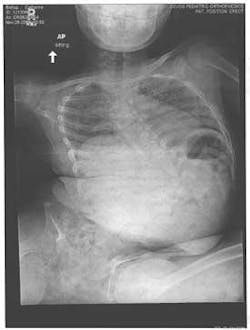

Catherine was brought to me by her foster parents, Jan and Harold Woods, facing the biggest challenge of her life. Her affliction was compromising her internal organs to the degree that she required corrective surgery to have any hope of continuing to live. Her surgeon mandated that if he was to be successful placing the titanium rods along her spine to straighten her back and increase the volume in her thoracic cavity, her body must be disease-free. Both he and her foster parents knew the oral cavity was going to be a challenge.